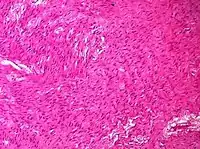

| Sex cord-stromal tumor | Ovarian fibroma | 1.5% | 0% | Spindle-shaped fibroblastic cells and abundant collagen.[8] |  |